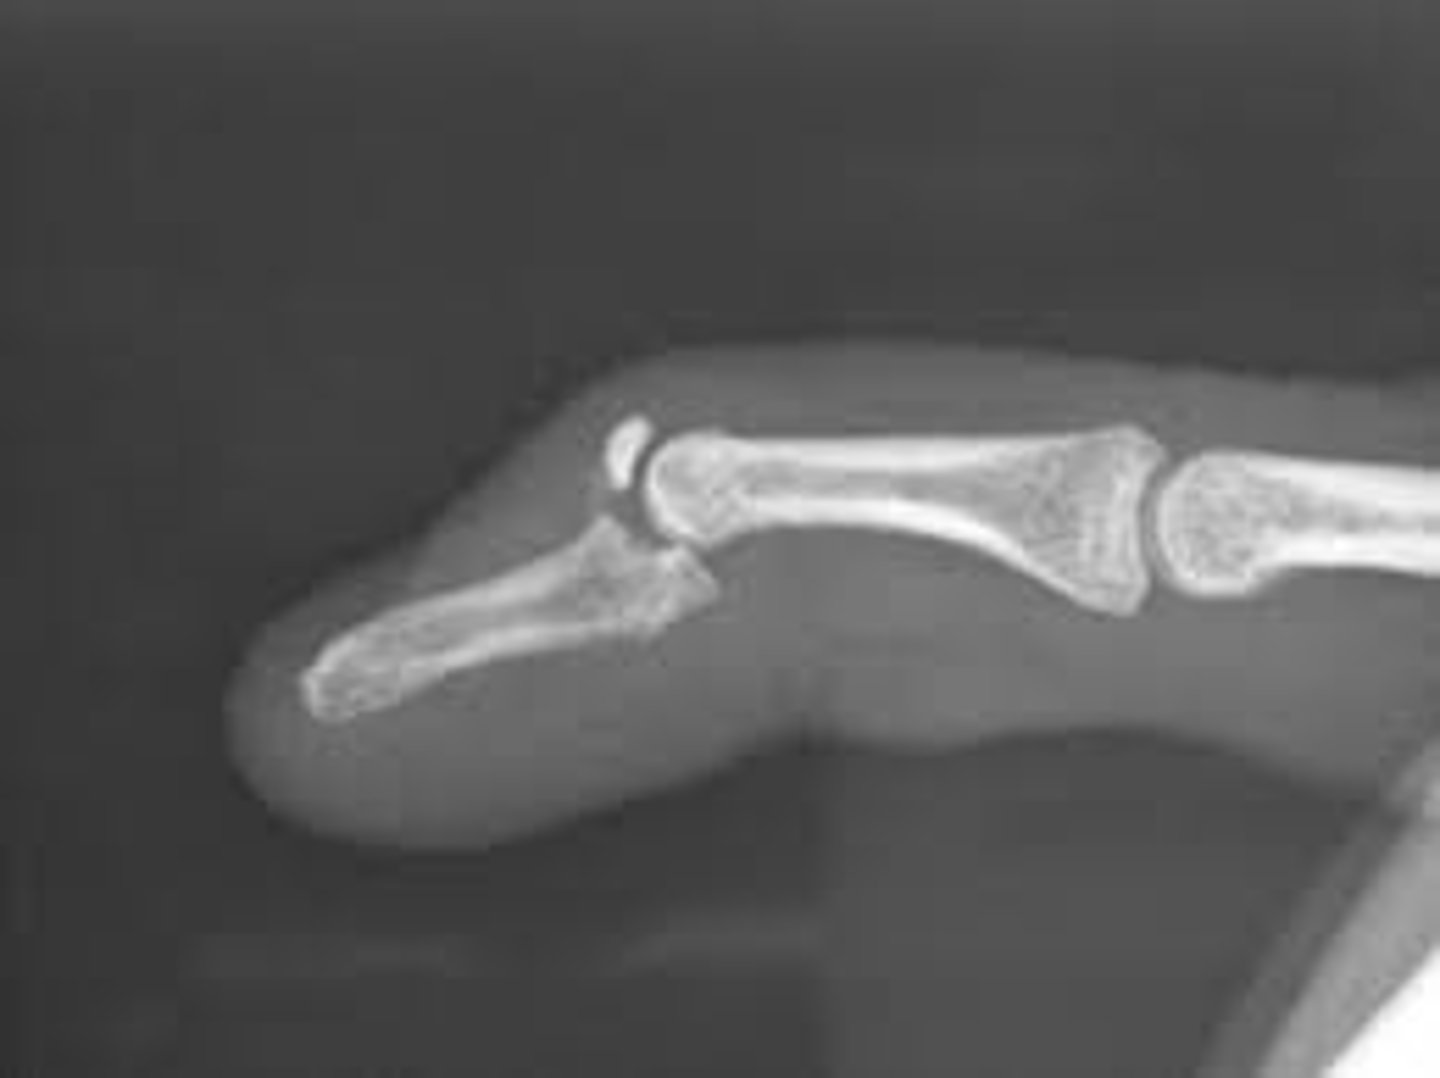

Fracture of the distal phalanx with finger extended

Baseball fx